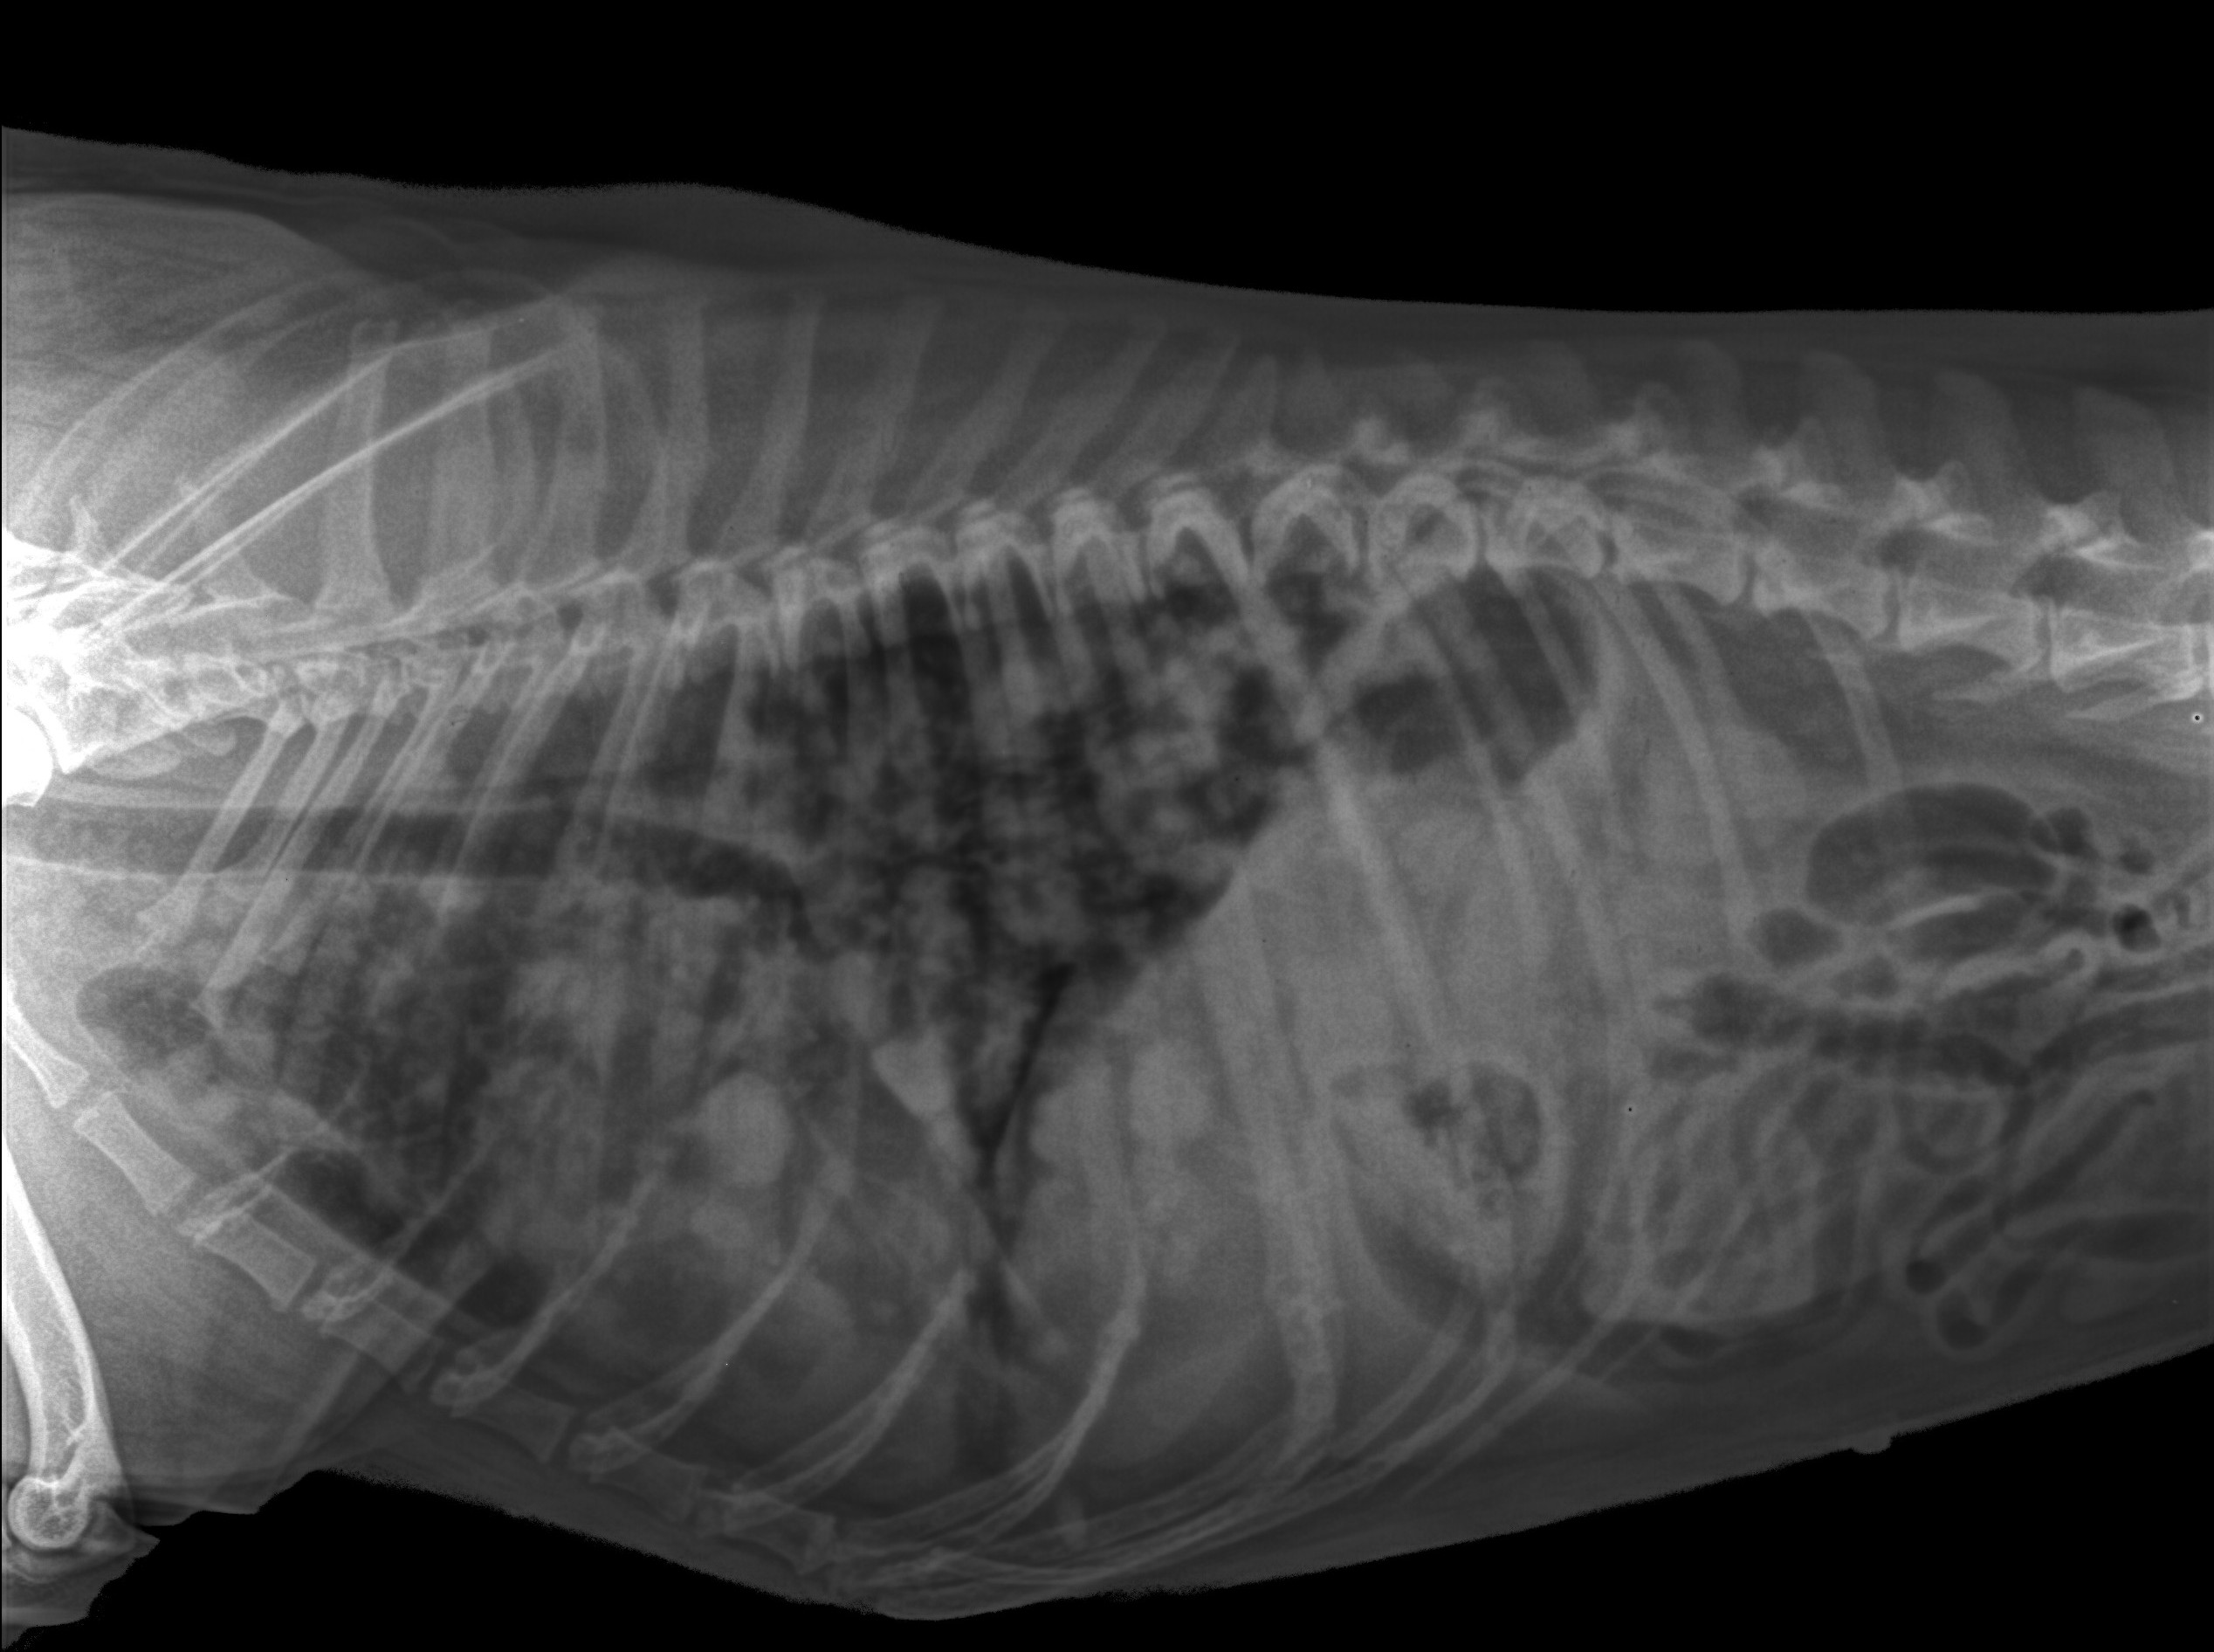

Puppies Respiratory Rate Pet Breathing Issues Evansville Chateau Why Do Dogs Take Deep Breaths If you notice that your dog is taking short, quick breaths, it can be a cause for concern. Heavy breathing in dogs is characterized by rapid, labored, or strained breaths and can suggest an inadequate oxygen supply. Heavy breathing in dogs can be a sign of serious medical conditions, such as heart failure, pneumonia, cancer, or trauma. Heavy breathing in. Why Do Dogs Take Deep Breaths.